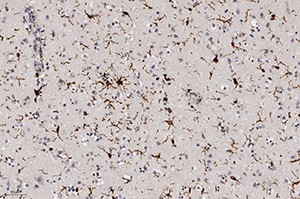

Рисунок 3. Поражение астроцитов, тучные астроциты (окраска по методу Клювера — Барреры, ґ200).В то же время в ганглиозных клетках коры больших полушарий преобладали ишемические изменения (по Шпильмейеру) без характерной ядерной патологии.

Рисунок 8. Активация микроглии (ИГХ (Iba-1), ґ200).Окраска на микроглию при ИГХ (Iba-1) показала их активацию, что свидетельствовало об иммунном ответе ткани мозга на данную инфекцию, а также активацию периваскулярных астроцитов (ИГХ к КГФБ) (см. рис. 8).